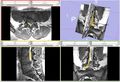

We are developing a nerve segmentation algorithm for the automatic isolation of nerves and nerve ganglia inside the spinal sack and out through the vertebrae in new MR Myelography images. Current progress can track the core of a Nerve.

Currently we use a particle-filter tracking approach for segmenting the nerves. The algorithm is given a seed point, preferably somewhere in the spine. The particles are tubes following Bézier curves (and hence forming a B-spline track). The dynamics model encourages continuity and smoothness. The image likelihood model compares gradient fields and intensities of predicted patches with image observations to evaluate a posterior distribution of the particles' importance. While we can currently usually track the nerve cores, usually fully throughout the vertebral canal, the algorithm does not delineate the full extent of the nerves and has sudden changes, and behaves poorly on peripheral nerves outside of the vertebral canal. We will modify the likelihood function and parameters and concentrate on achieving this during the project week.

• Sudden changes in the segmentation can be ameliorated. In general, can now constrain the radius function to be smoother in the general (visual) sense not just in the technical mathematical sense, to avoiding sudden changes in the segmentation (which are simply areas with fast but smooth radius function change).

• With careful characterization of the newer radius function, we can segment some of the thinner peripheral nerves. This is still specific to the images explored, but it can be done.

Results are attached: